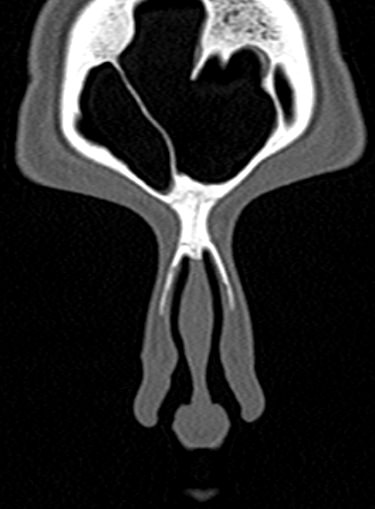

В современной отоларингологии широко применяется мультиспиральная компьютерная томография для диагностики различных заболеваний ЛОР-органов. КТ относится к лучевым методам исследования, который с помощью рентгеновских лучей позволяет получить детальное изображение костных структур, хрящей носа, околоносовых воздухоносных пазух и прилегающих областей.

Преимуществом КТ является ее способность отлично визуализировать кости лицевого черепа, что делает методику незаменимой для оценки любых травматических повреждений носа, выявления аномалий развития носовой перегородки и, деформации хрящей.

Аппараты сканируют область исследования в течение нескольких секунд, производя одномоментно от 64 до 128 тончайших срезов толщиной от 0,5 мм. Высокая скорость сканирования обеспечивает минимальную дозу облучения для пациента. При этом получаются четкие изображения с высоким контрастным разрешением, что дает возможность рассмотреть исследуемую зону в мельчайших подробностях. Кроме того, томографы создают объемные 3D-изображения области носа и прилегающих пазух, что помогает в оценке пространственного соотношения анатомических структур, выявленной патологии и способствует проведению точной диагностики.

Что показывает КТ носа

- полипы;

- опухоль (злокачественная и доброкачественная);

- инородные тела в указанной области;

- воспалительный процесс (утолщение слизистой оболочки, жидкость, признаки гноя);

- повреждение костей.